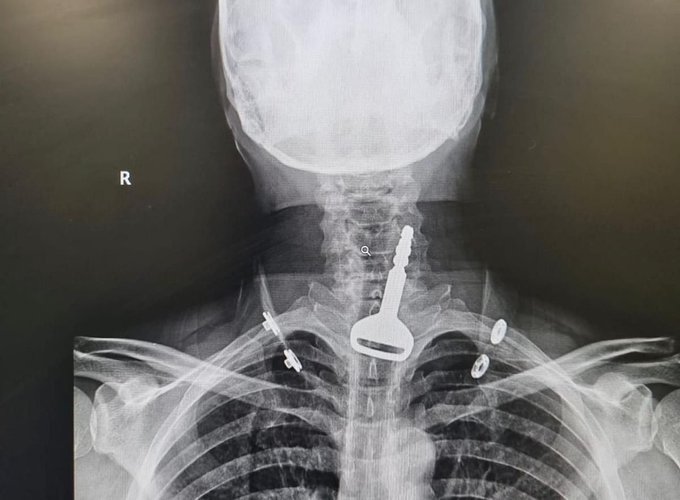

القنفذة.. تدخّل جراحي يُنقذ حياة مريض ابتلع مفتاح سيارته

نجح فريق طبي بمحافظة القنفذة في استخراج مفتاح سيارة من الجهاز التنفسي لمريض أربعيني كاد أن يودي بحياته، في عملية استغرقت 15 دقيقة عن طريق المنظار.

وأكدت “الصحة” في القنفذة أن الفرق الطبية تمكنت ولله الحمد من إنقاذ حياة مريض بعمر 49 عامًا أحضر لقسم الطوارئ يعاني من انسداد بمجرى التنفس، حيث اتضح بعد إجراء الفحص السريري والإشعاعي وجود مفتاح سيارة بمجرى التنفس.

وقال الفريق الطبي المشرف على الحالة: إن المريض كان يلهو بالمفتاح حسب ما توضح خلال الكشف، حيث تقرر فورًا إدخال المريض قسم العمليات وتكثيف العناية الصحية له؛ لكونه مريض قلب، وتم إجراء التدخل الجراحي عن طريق المنظار واستخراج المفتاح، ومن ثم متابعة الحالة عن طريق قسم التنويم لحين استقرار حالته الصحية وخروجه بالسلامة.